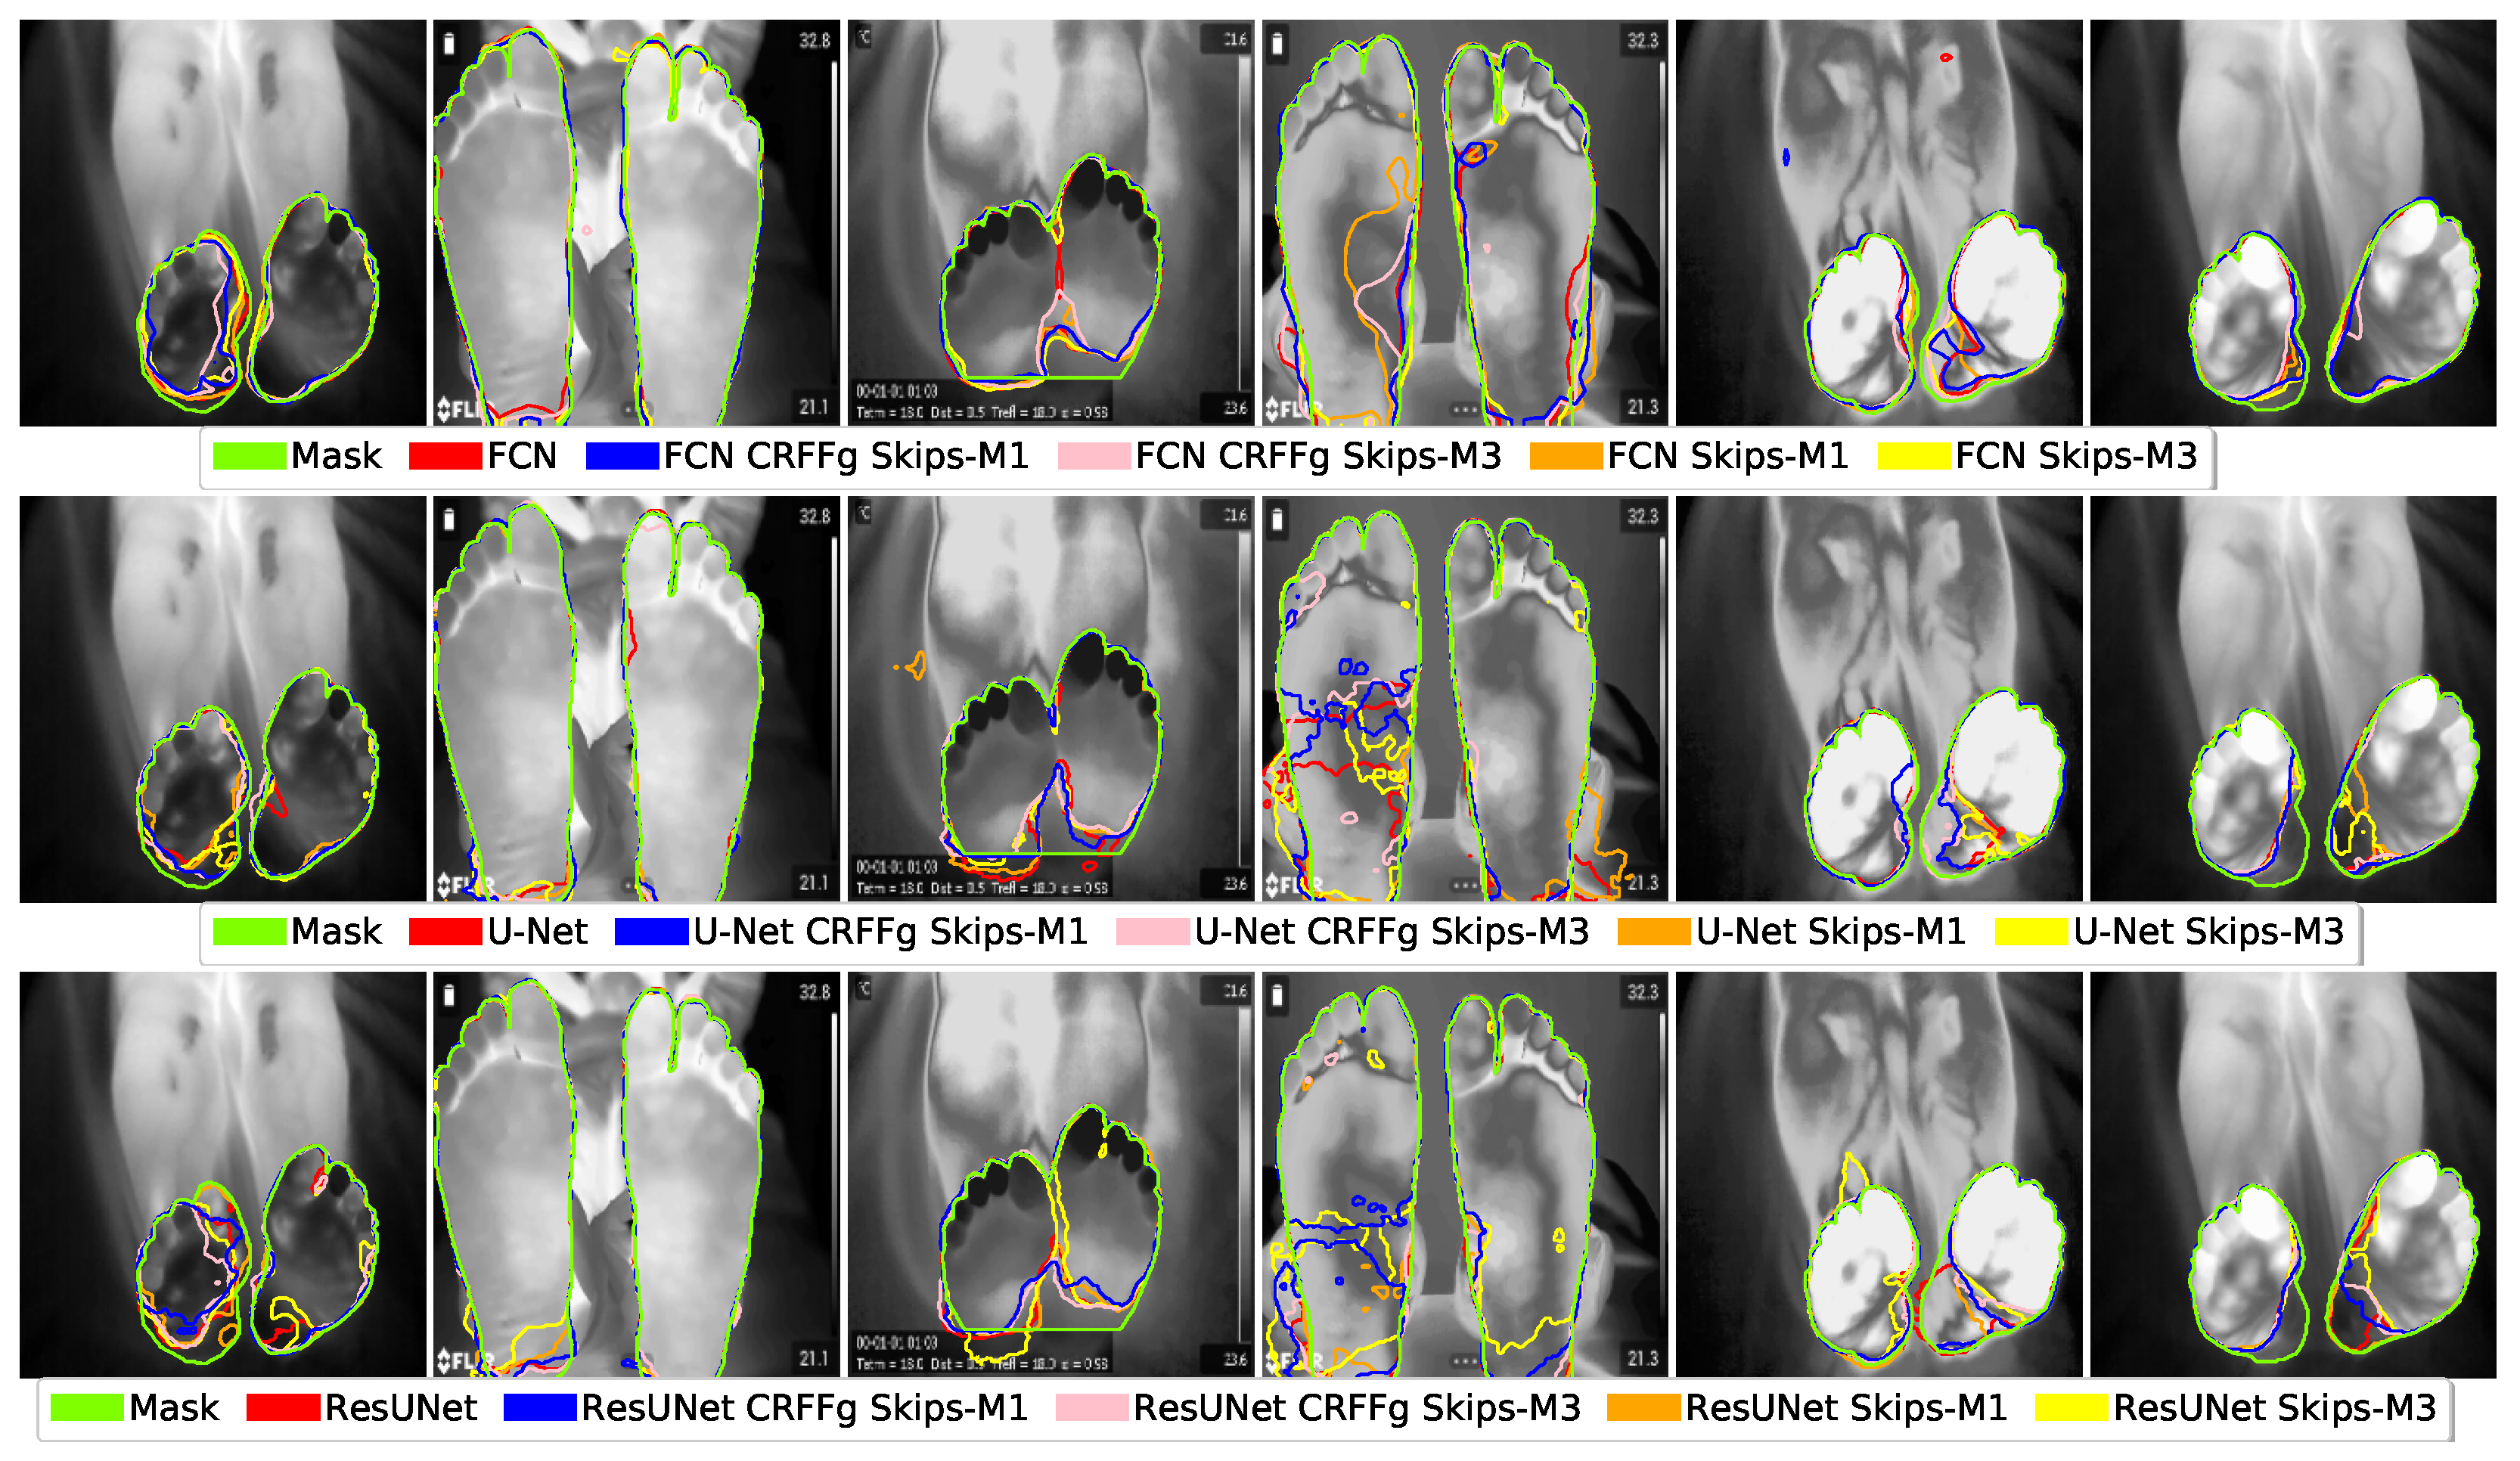

4.1. Visual Inspection Results